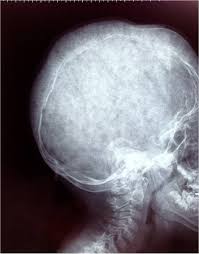

DIAGNOSTICO

Radiografía simple de cráneo

Tomografía computerizada de cráneo

Resonancia magnética nuclear (RMN):